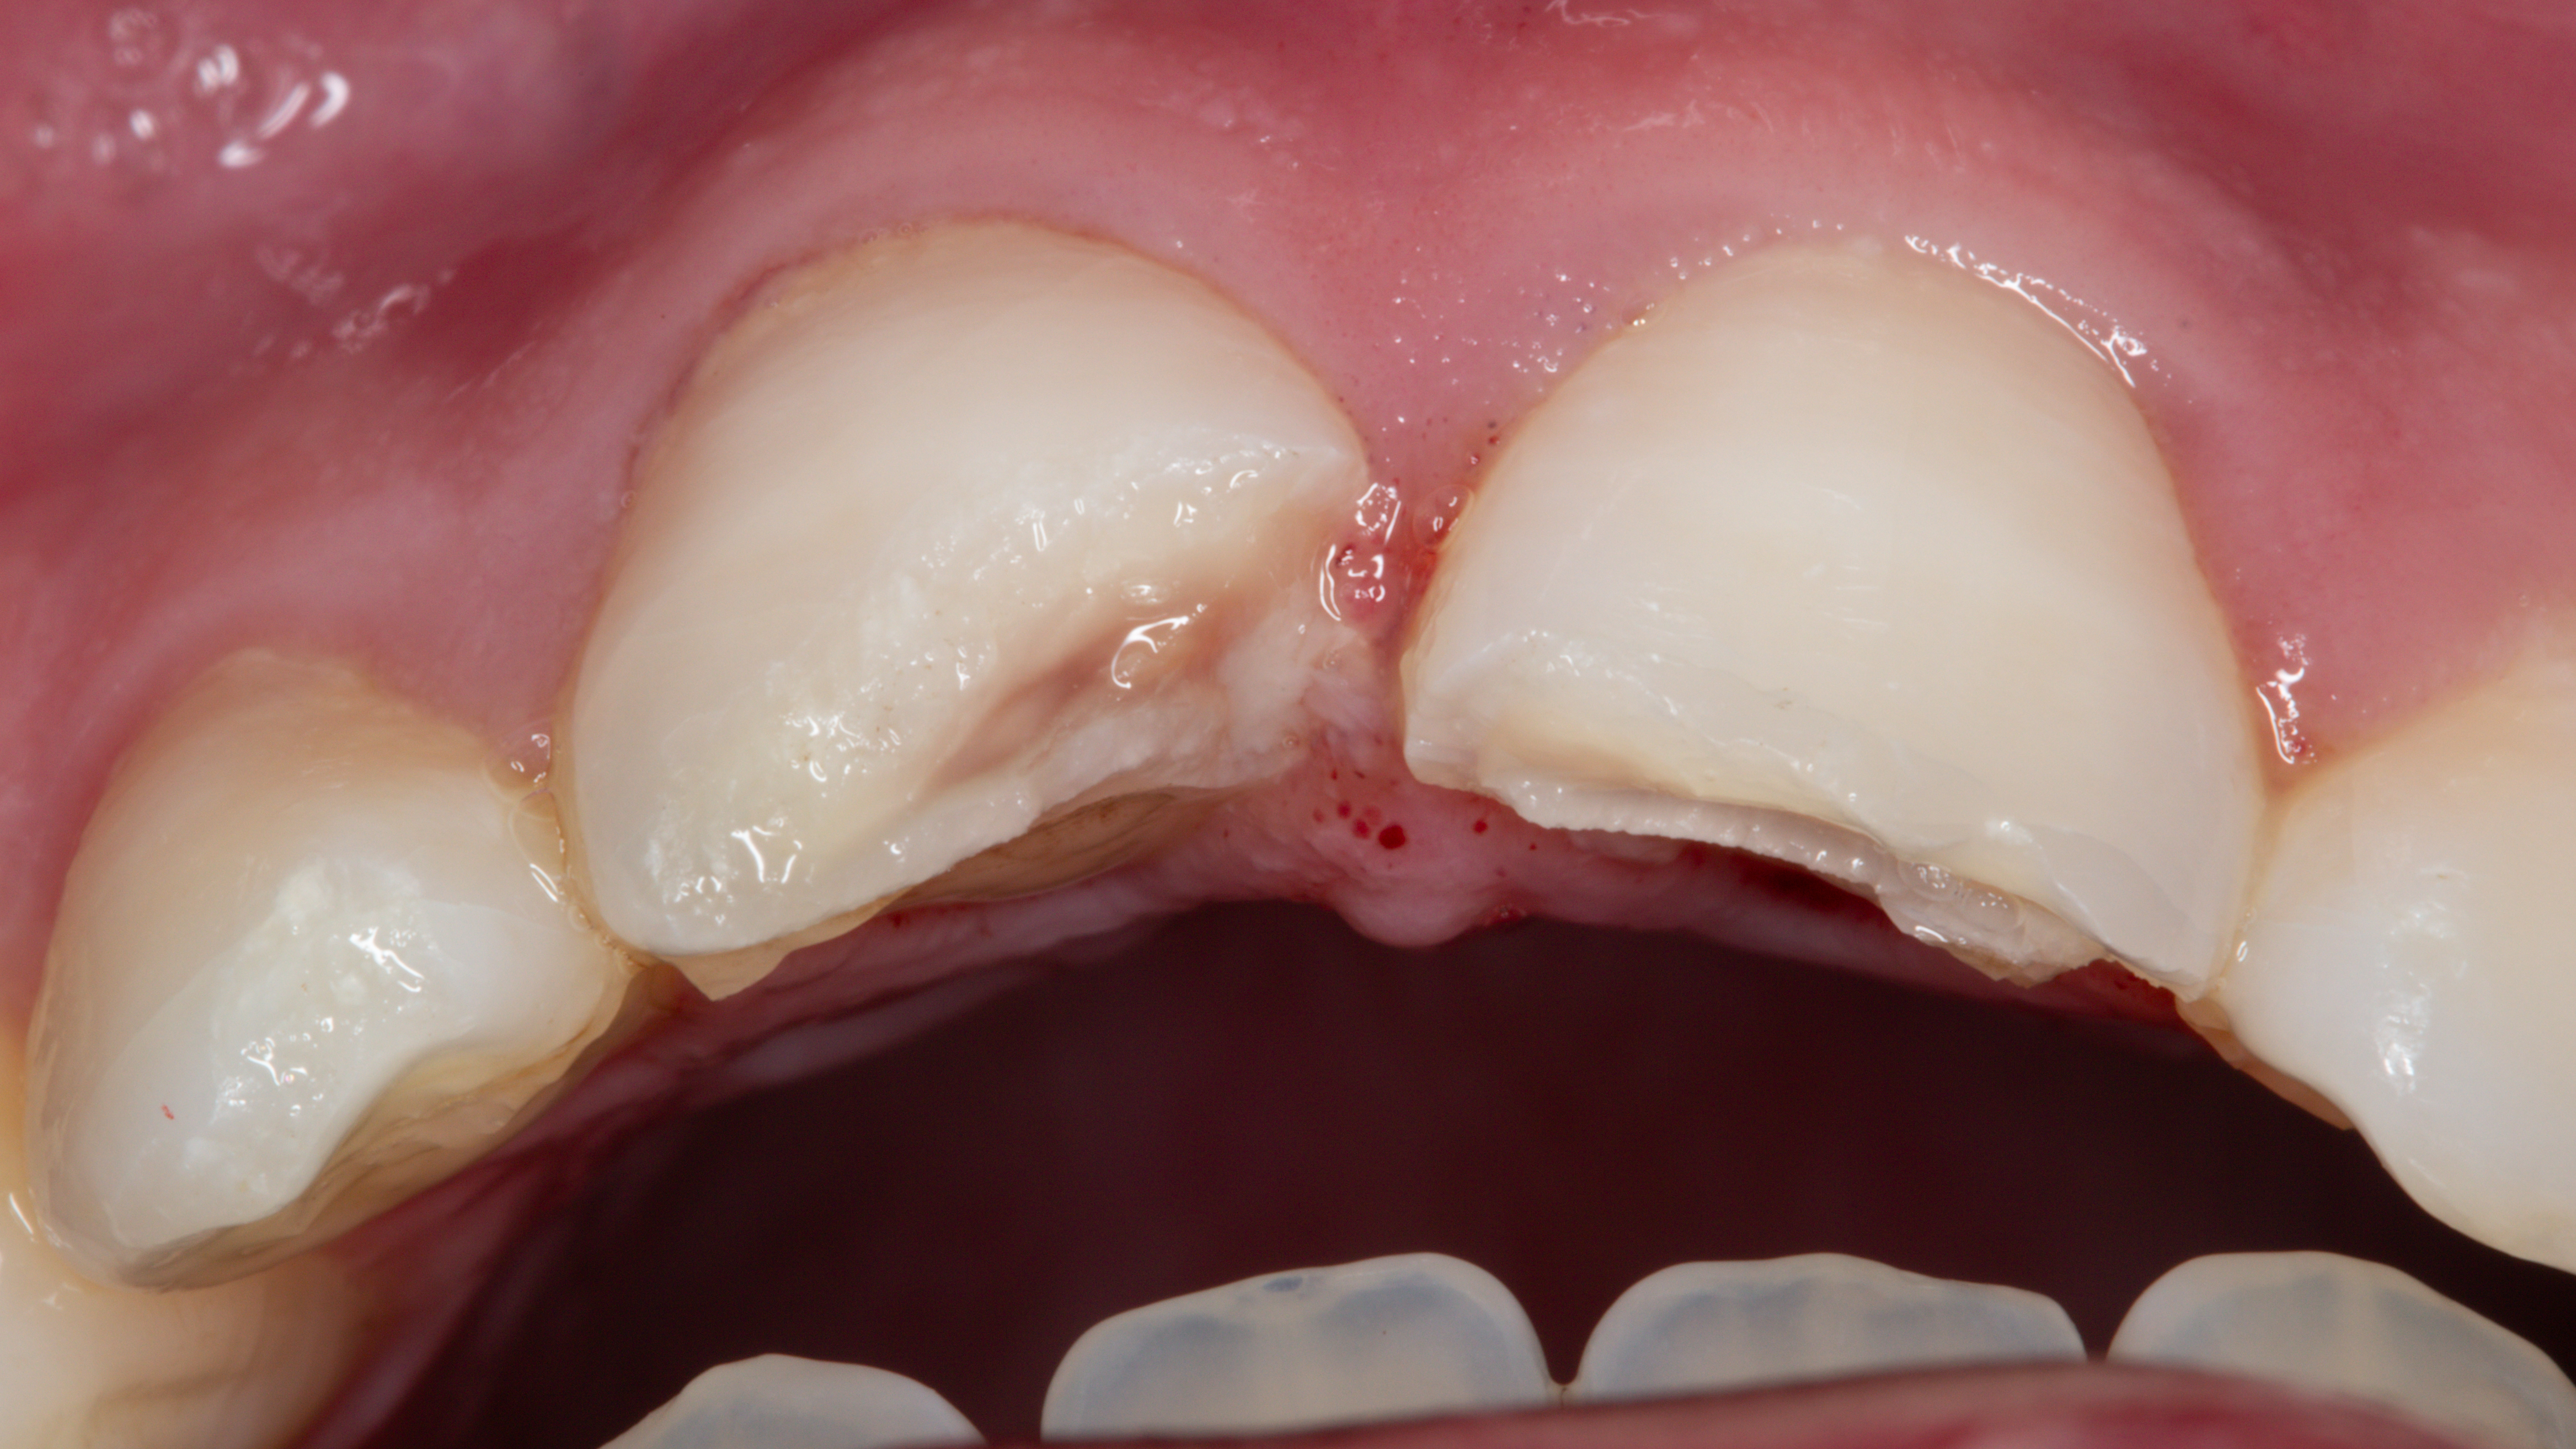

W badaniu widoczne było złamanie zębów 11 i 21 w obrębie szkliwa i zębiny bez obnażenia miazgi oraz złamanie w obrębie szkliwa zębów 12 i 22 (ryc. 1 i 2).

Zęby 11 i 21 nie reagowały na zimno, były bolesne opukowo i przy dotyku, ale nie wykazywały zwiększonej ruchomości. Zęby 12 i 22 nie wykazały odchyleń od normy przy opukiwaniu, reakcji na zimno ani w zakresie ruchomości. Pacjent podawał brak kontaktów zgryzowych……..